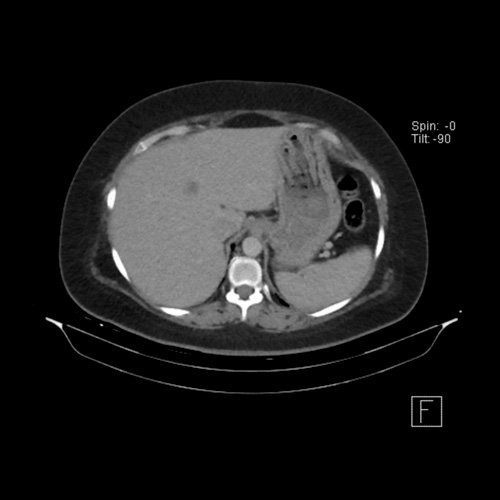

Tomografía de abdomen y pelvis sin contraste oral con contraste EV (12/02/26): El hígado es de forma, tamaño y situación habituales. Su superficie es lisa, y sus bordes son agudos. Imagen hipovascular aislada de 15 mm en segmento V de aspecto inespecífico. Sugiero complementar con RMI. La vía biliar intra y extrahepática es de calibre conservado. La vesícula biliar es de forma, tamaño y situación normales, sin imágenes que sugieran la presencia de litiasis. Tener en cuenta que este método puede pasar por alto litiasis colesterínicas. El bazo es de forma, tamaño y situación normales. El páncreas es de características normales. El conducto de Wirsung es de calibre conservado. Adenoma adrenal izquierdo de 16 mm. Ambos riñones son de forma, tamaño y situación habituales. Concentran y eliminan adecuadamente la sustancia de contraste. Sin evidencia de alteraciones calicopiélicas ni ureterales. La aorta, las arterias ilíacas primitivas, internas, externas y femorales, son de calibre y trayecto conservado, permeables. La vena cava inferior y las venas ilíacas primitivas, internas, externas y femorales son de calibre y trayectoria conservados, permeables. No se observan adenomegalias intraperitoneales, retroperitoneales, ilíacas ni inguinales. No se observan alteraciones a nivel del tracto gastrointestinal. La vejiga es de paredes lisas, sin presentar efectos de masa endoluminales ni parietales. Utero en AVF, lateralizado a izquierda. Pequeña hernia umbilical de contenido graso y escaso líquido intrasacro. No se identifican alteraciones en las estructuras óseas visualizadas.

TC de abdomen y pelvis con contraste endovenoso (12/02/2026) Corte axial: adenoma adrenal izquierdo de 16 mm.

TC de abdomen y pelvis con contraste endovenoso (12/02/2026) Corte coronal: adenoma adrenal izquierdo de 16 mm.